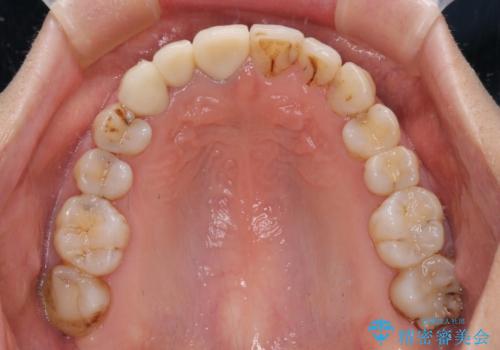

前歯のむし歯治療の跡や奥歯の目立つ銀歯がなくなり、明るい口元になりました。